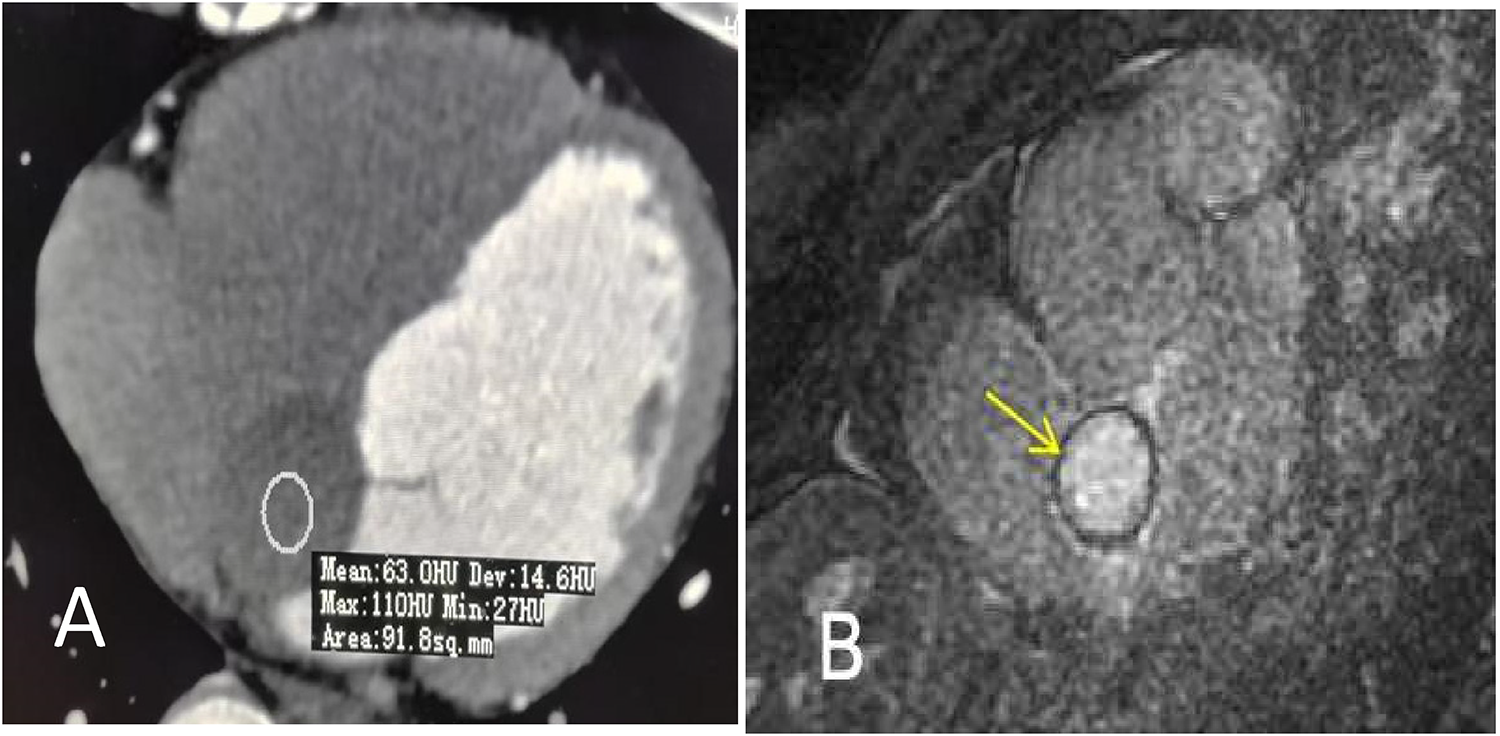

A 47-year-old man presented to a local clinic with complaints of palpitation. Physical examination and chest radiography were unremarkable; however, a 12-lead electrocardiogram (ECG) showed a third-degree atrioventricular block (Figure 1A). Transthoracic echocardiography (TTE) revealed normal ventricular and valve function; however, a well-demarcated hypoechoic ovoid mass measuring 29.9 mm × 25.6 mm was identified in the interatrial septum (IAS) (Figure 2A). In addition, transesophageal echocardiography (TEE) revealed a large, homogeneous, hypoechoic mass in the near field on mid-esophageal views (Figure 2B). The mass had no stalk, and color Doppler echocardiography revealed no color flow signal within the mass. Myocardial contrast echocardiography (MCE) revealed a hypoechogenic mass in the atrial septum, with clear and regular boundaries and no obvious contrast agent perfusion (Figure 2C). Three-dimensional TEE demonstrated the relationship between the mass and surrounding structures (Figure 2D). Subsequent computed tomography (CT) (SOMATOM Definition Flash) coronary angiography revealed no obvious stenosis in the left main coronary artery, anterior descending branch, circumflex branch, or right coronary arteries. A low-density ovoid mass was found in the atrial septum, with well-defined borders, no significant enhancement, and an absence of feeding vessels from the coronary arteries (Figure 3A). Magnetic resonance imaging (MRI) (SIGNA EXCITE HD 1.5 T) identified a mass in the atrioventricular septal region (Figure 3B). Neither fat deposition nor late gadolinium enhancement were observed in the tumor. Based on multimodality imaging, the mass was most likely consistent with a cyst.

Figure 3

(A) Contrast-enhanced CT shows a low-intensity ovoid nodule without obvious enhancement at the interatrial septum (arrow). The mean attenuation value was approximately 63 Hu. (B) Cardiac MRI shows a round mass in the interatrial septum measuring 30 mm × 20 mm (arrow). Neither fat deposition nor late gadolinium enhancement were identified in the tumor.